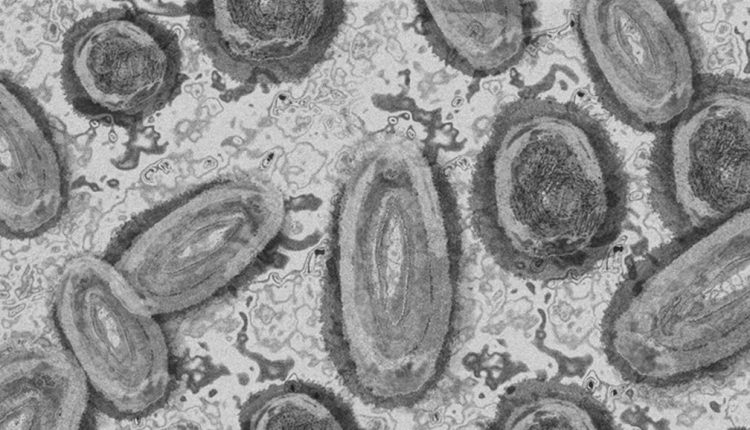

على عكس SARS-CoV-2، فإن فيروس جدري القرود هو فيروس DNA (أو فيروس الحمض النووي الريبوزي)، إذ يتم ترميز جينومه بحوالي 200000 وحدة وراثية، بينما جينوم SARS-CoV-2 أصغر بكثير حوالي 30000 وحدة.

رئيس أمانة الجدري بمنظمة الصحة العالمية روزاموند لويس، قال في جلسة أسئلة وأجوبة عامة عبر الإنترنت؛ إن فيروسات الحمض النووي هذه تميل إلى عدم التحور، وتميل إلى أن تكون مستقرة إلى حد ما وأقل احتمالا لتوليد متغيرات.